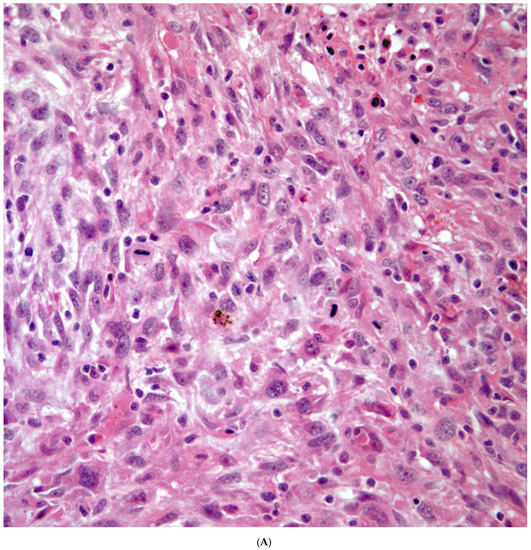

Sarcomatoid carcinomas: These tumors show a tightly packed spindle cell proliferation composed of slender cells with fusiform nuclei and inconspicuous nucleoli, replacing normal lung parenchyma. The tumors are well delimited but not encapsulated (Figure 1). Cellular atypia is variable and may show areas of mild to moderate to marked atypia. Mitotic figures also vary and may be inconspicuous or may be evident with the presence of atypical mitotic figures (Figure 2A,B). In high-grade tumors, the presence of necrosis and hemorrhage is prominent and is mixed with the neoplastic component. Important to recognize is that sarcomatoid carcinomas may be associated with areas of otherwise conventional non-small cell carcinoma such as adenocarcinoma or squamous cell carcinoma (Figure 3A,B). In addition, sarcomatoid carcinoma may also show the presence of bizarre giant cells admixed with the spindle cell component (pleomorphic carcinoma) (Figure 4).

(A) Atypia and mitotic activity. (B) Neoplastic spindle cell proliferation.